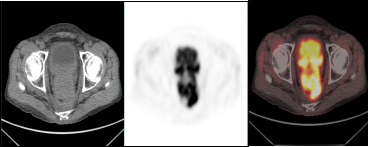

双癌检出:通过PET/CT一站式检查,同时检出两种肿瘤:甲状腺癌(绿色箭头)及子宫内膜癌(红色箭头),有利于临床治疗方案选择。

前列腺癌治疗后复发:18F-PSMA PET/CT显像示前列腺癌去势治疗术后复发并骶尾椎骨转移瘤。